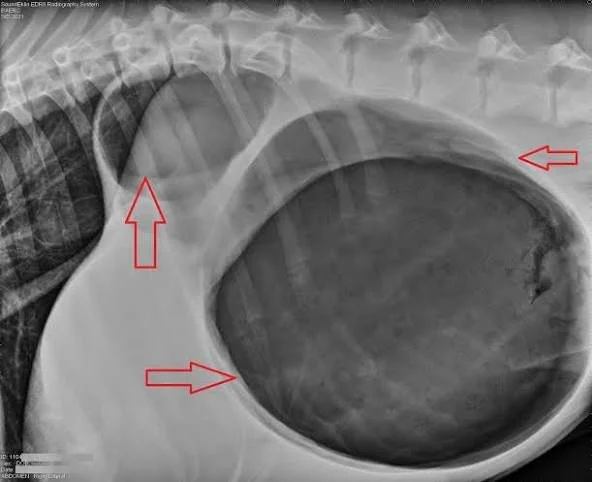

X-rays

Radiographs are the most common diagnostic tool used to confirm GDV.

X-rays can reveal the characteristic twisted stomach.